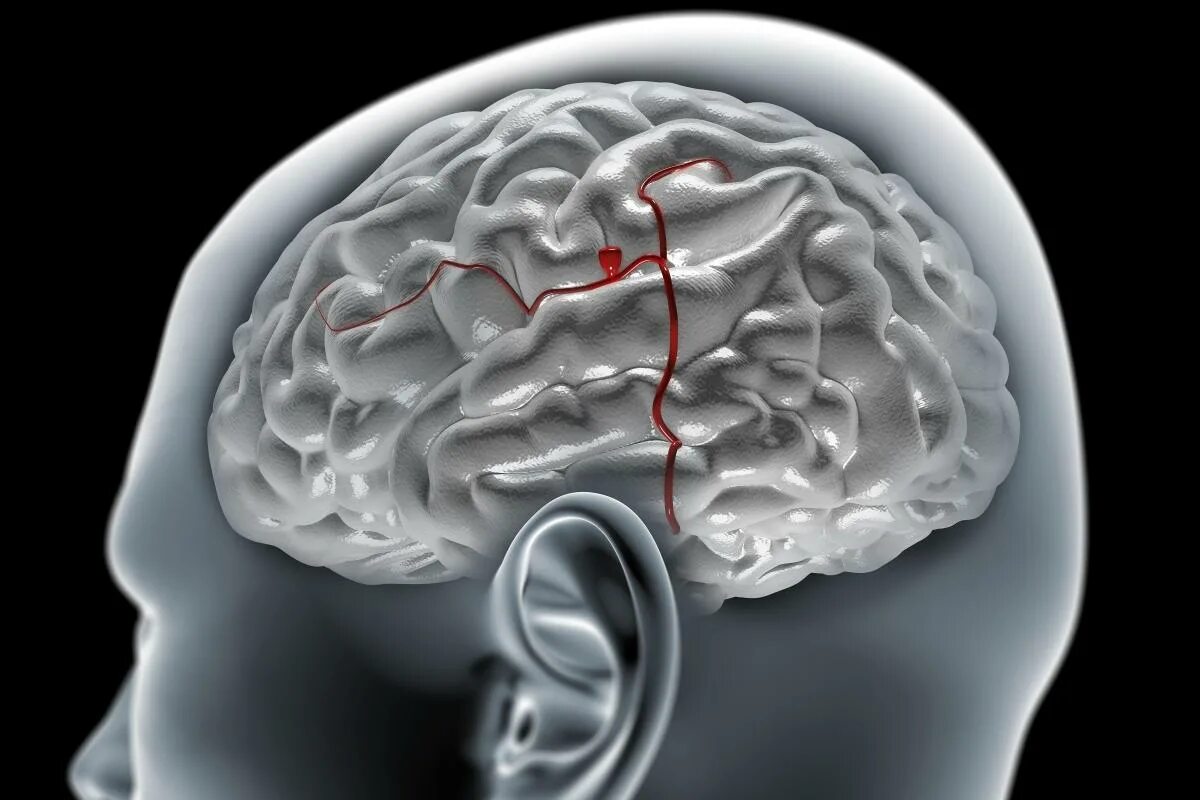

Аневризма сосудов мозга симптомы